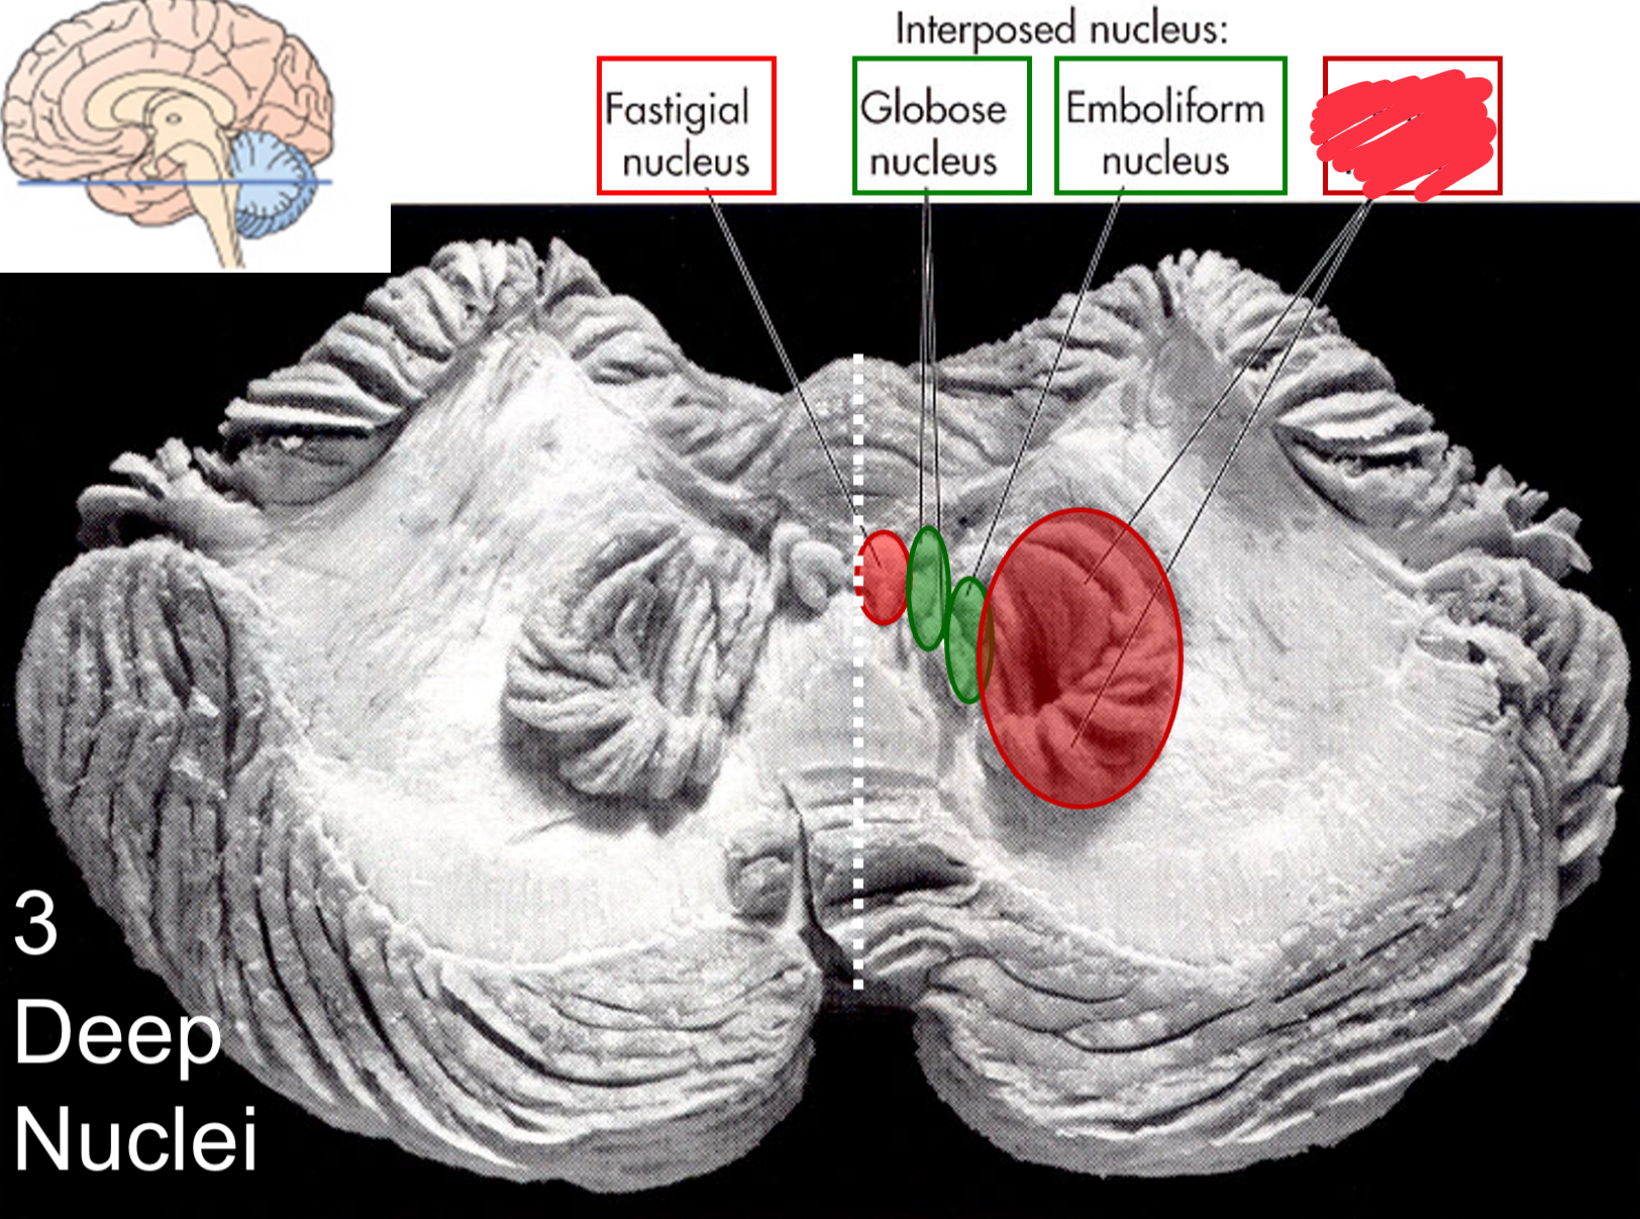

fastigial nucleus

interposed nucleus (globose + emboliform)

dentate nucleus